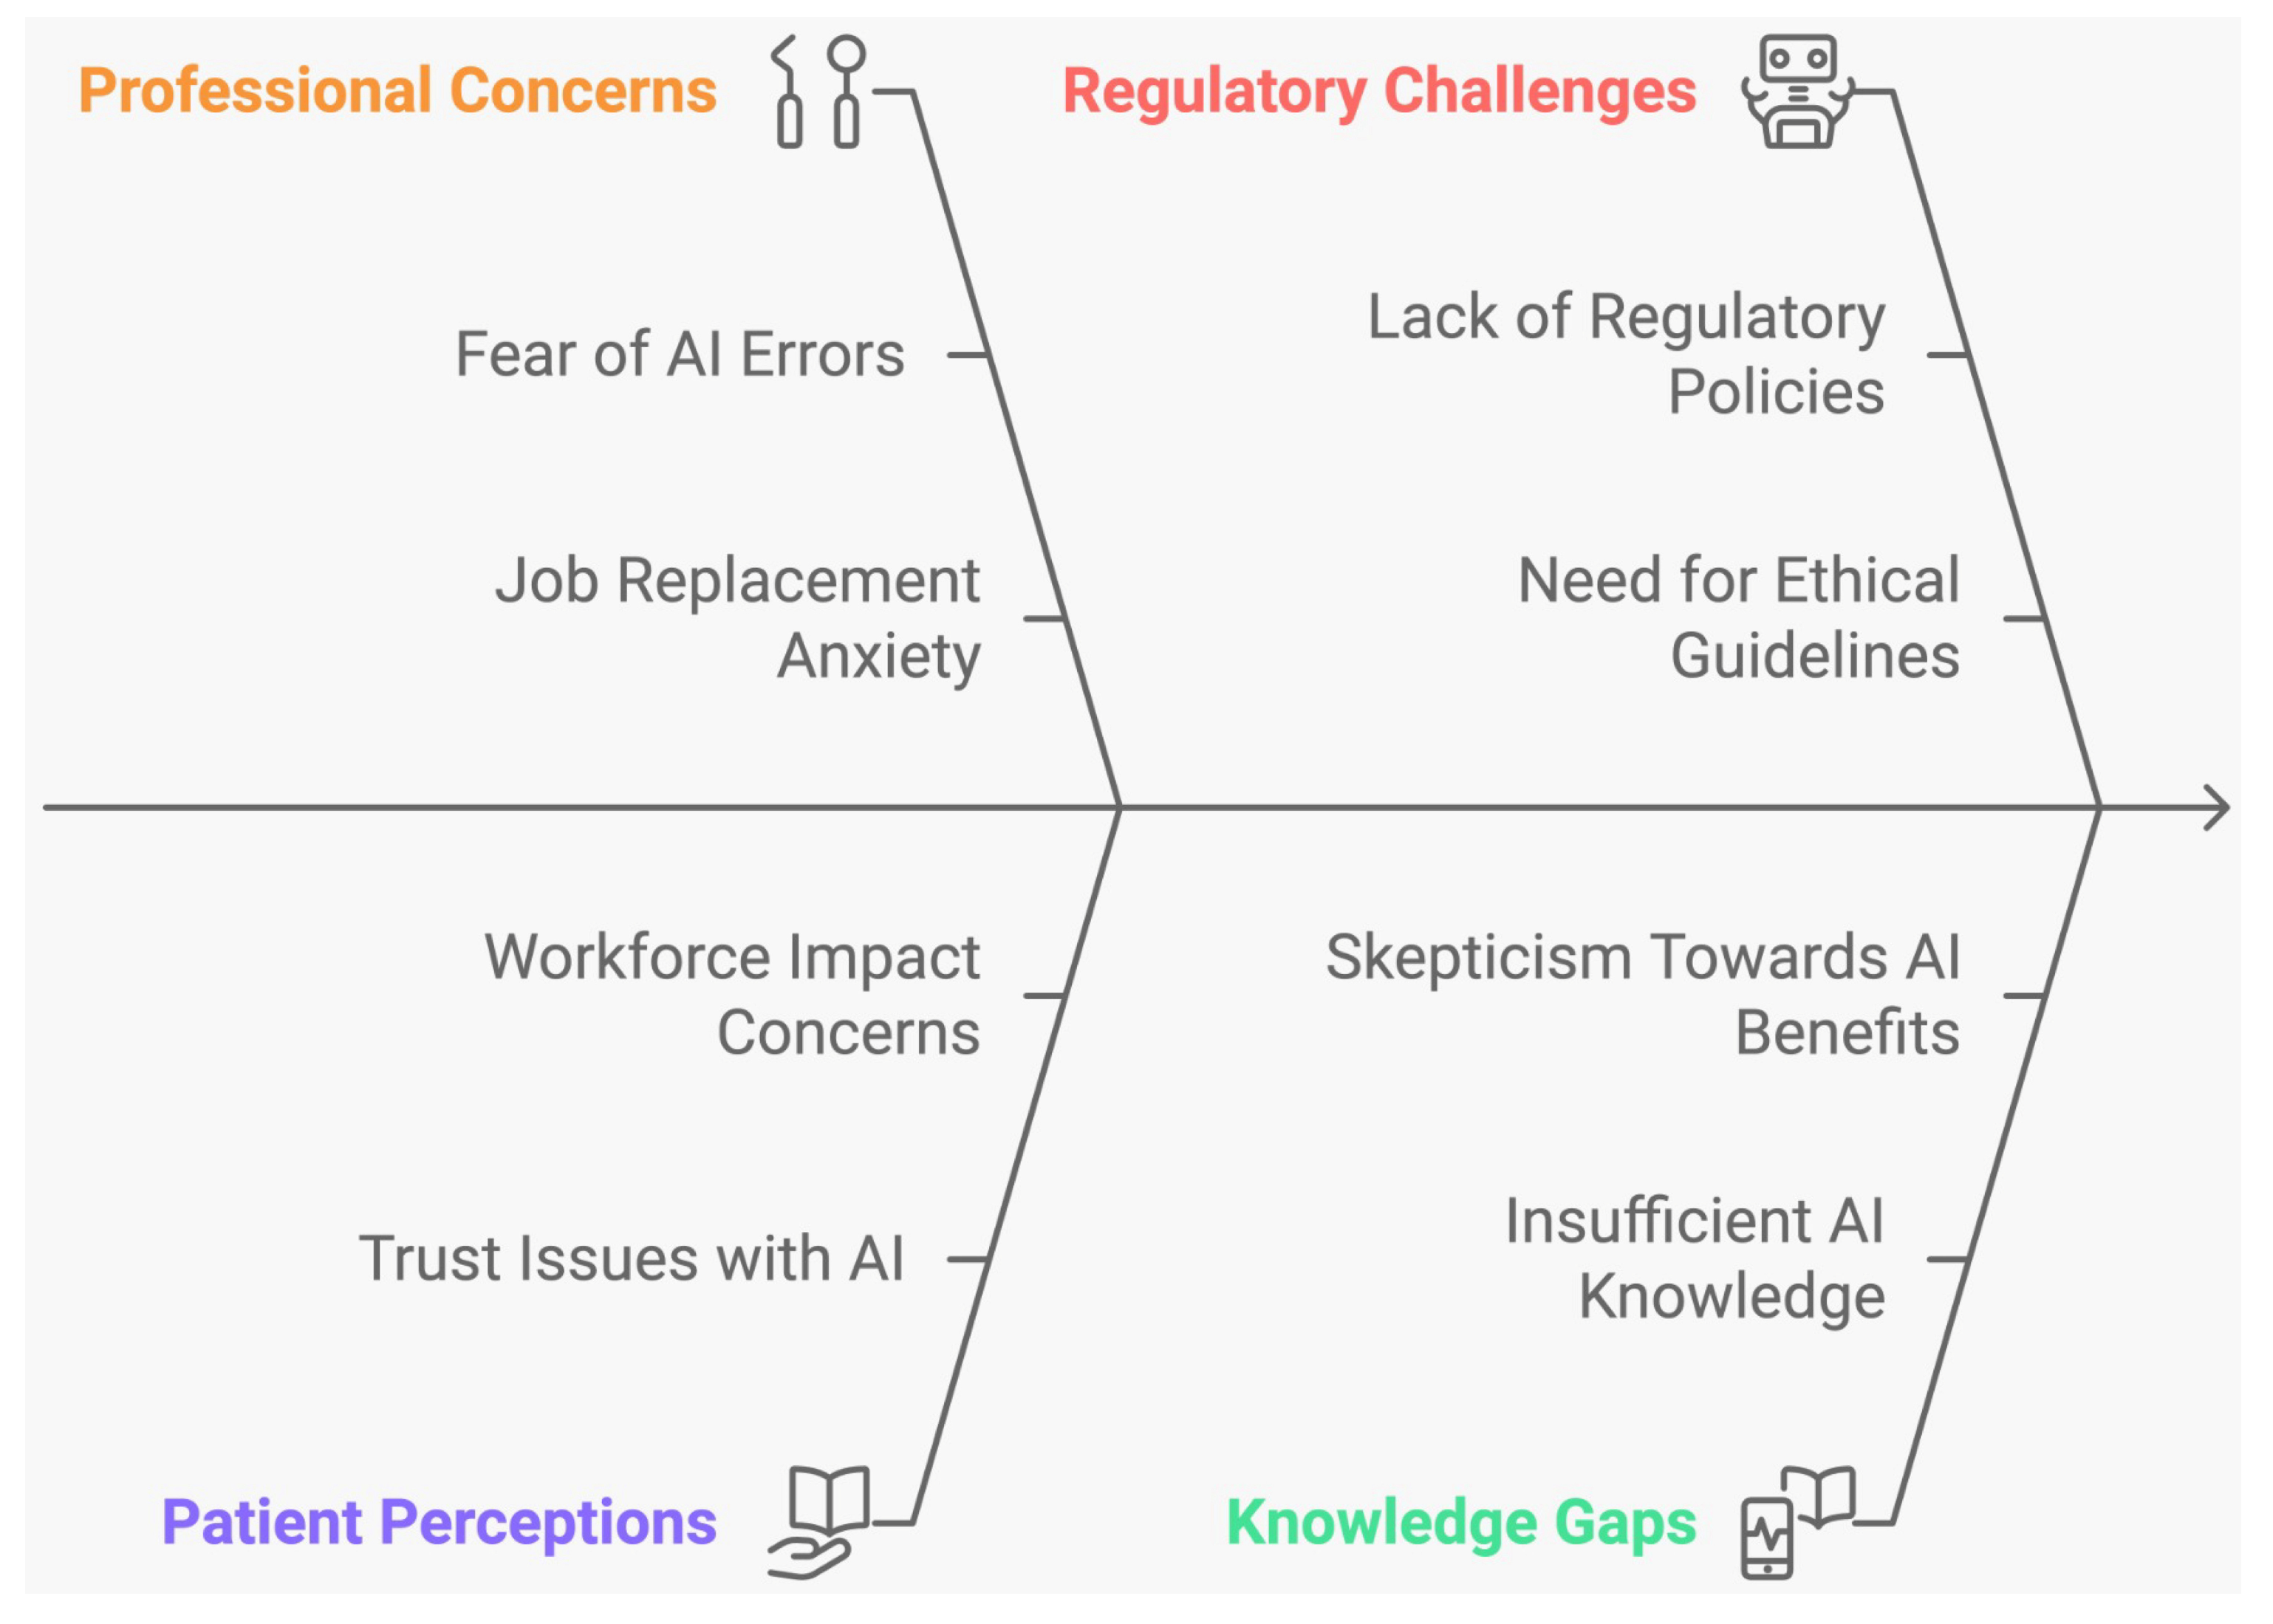

3.2. Ethical Issues Associated with the Use of AI in Dentistry

Characteristics of Included Studies

4.2. Ethical Issues Associated with the Use of AI in Dentistry

Limitations of Studies